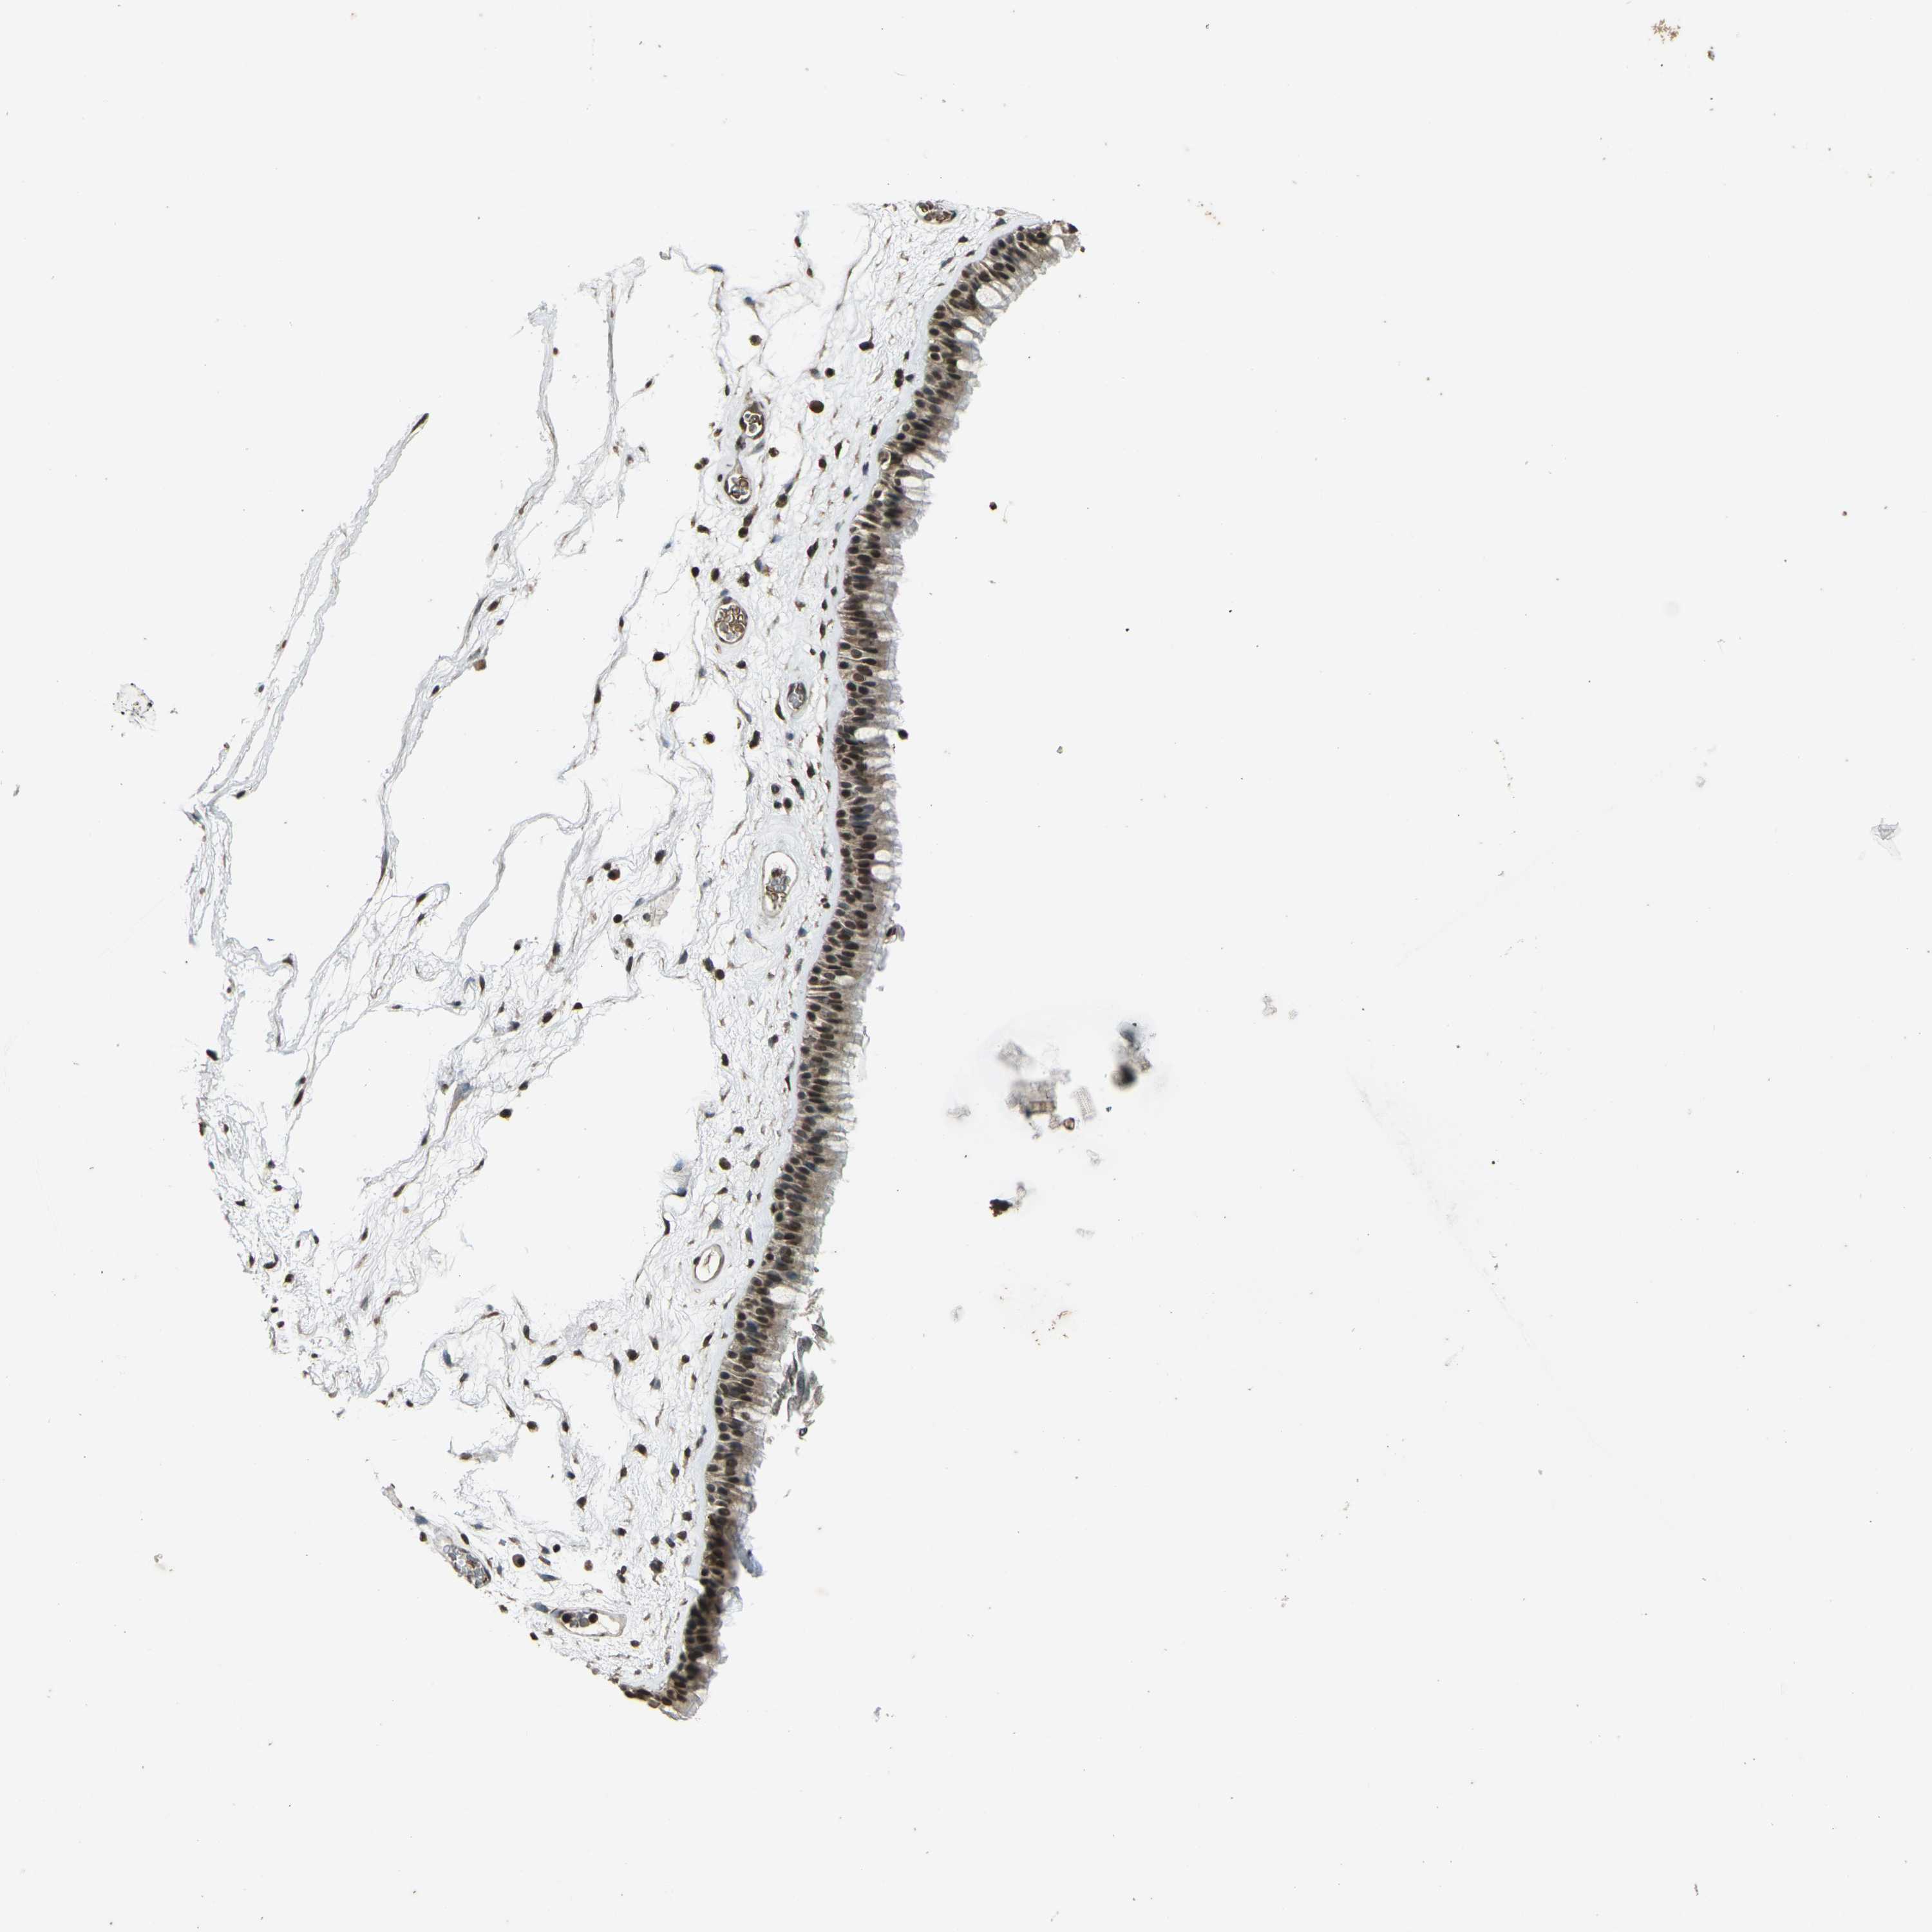

PRPF8